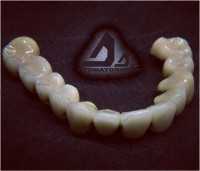

Протезирование зубов

| Установка коронки на зуб | от 5 000 ₽ до 40 000 ₽ |